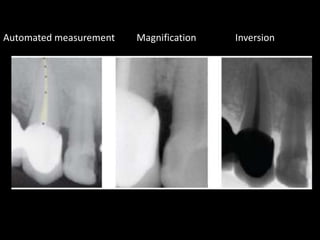

4. Digital radiography provides advantages like automated measurements and image manipulation but has higher initial costs and bulkier sensors.